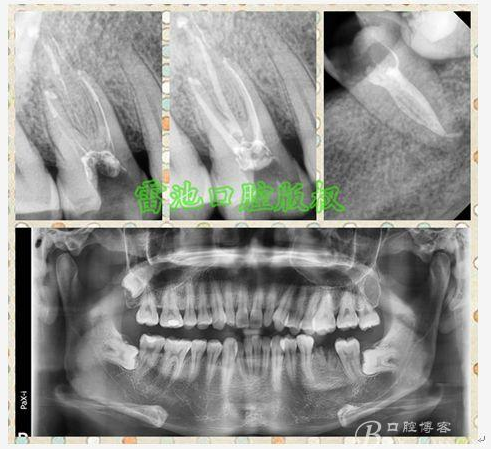

其實不管什么原因,最常用的問診與臨床理化檢查再結合影像學檢查都非常很重要,比如疼痛性質,冷熱診,扣診,壓診,活力測定,牙膠尖插入瘺管的病源定位,麻醉的排除性診斷,常規(guī)的X片檢查以及CBCT的應用,雖然是老生常談,但萬變不離其宗,抓住了“宗”,就自然不怕“變”。

E 、X線影像學的檢查研判能力: 這點不需要強調太多,對于普通的非CBCT的二維影像對醫(yī)生讀片能力有一定的要求,有個逐步提高的過程,非一蹴而就,需要學會把二維的X線影像與三維的解剖結構進行良好的對應結合,對于某些鈣化的髓室底,應通過想象把根管口的分布、根管的走向以及各種變化通過想象投射到對應的髓室底上;